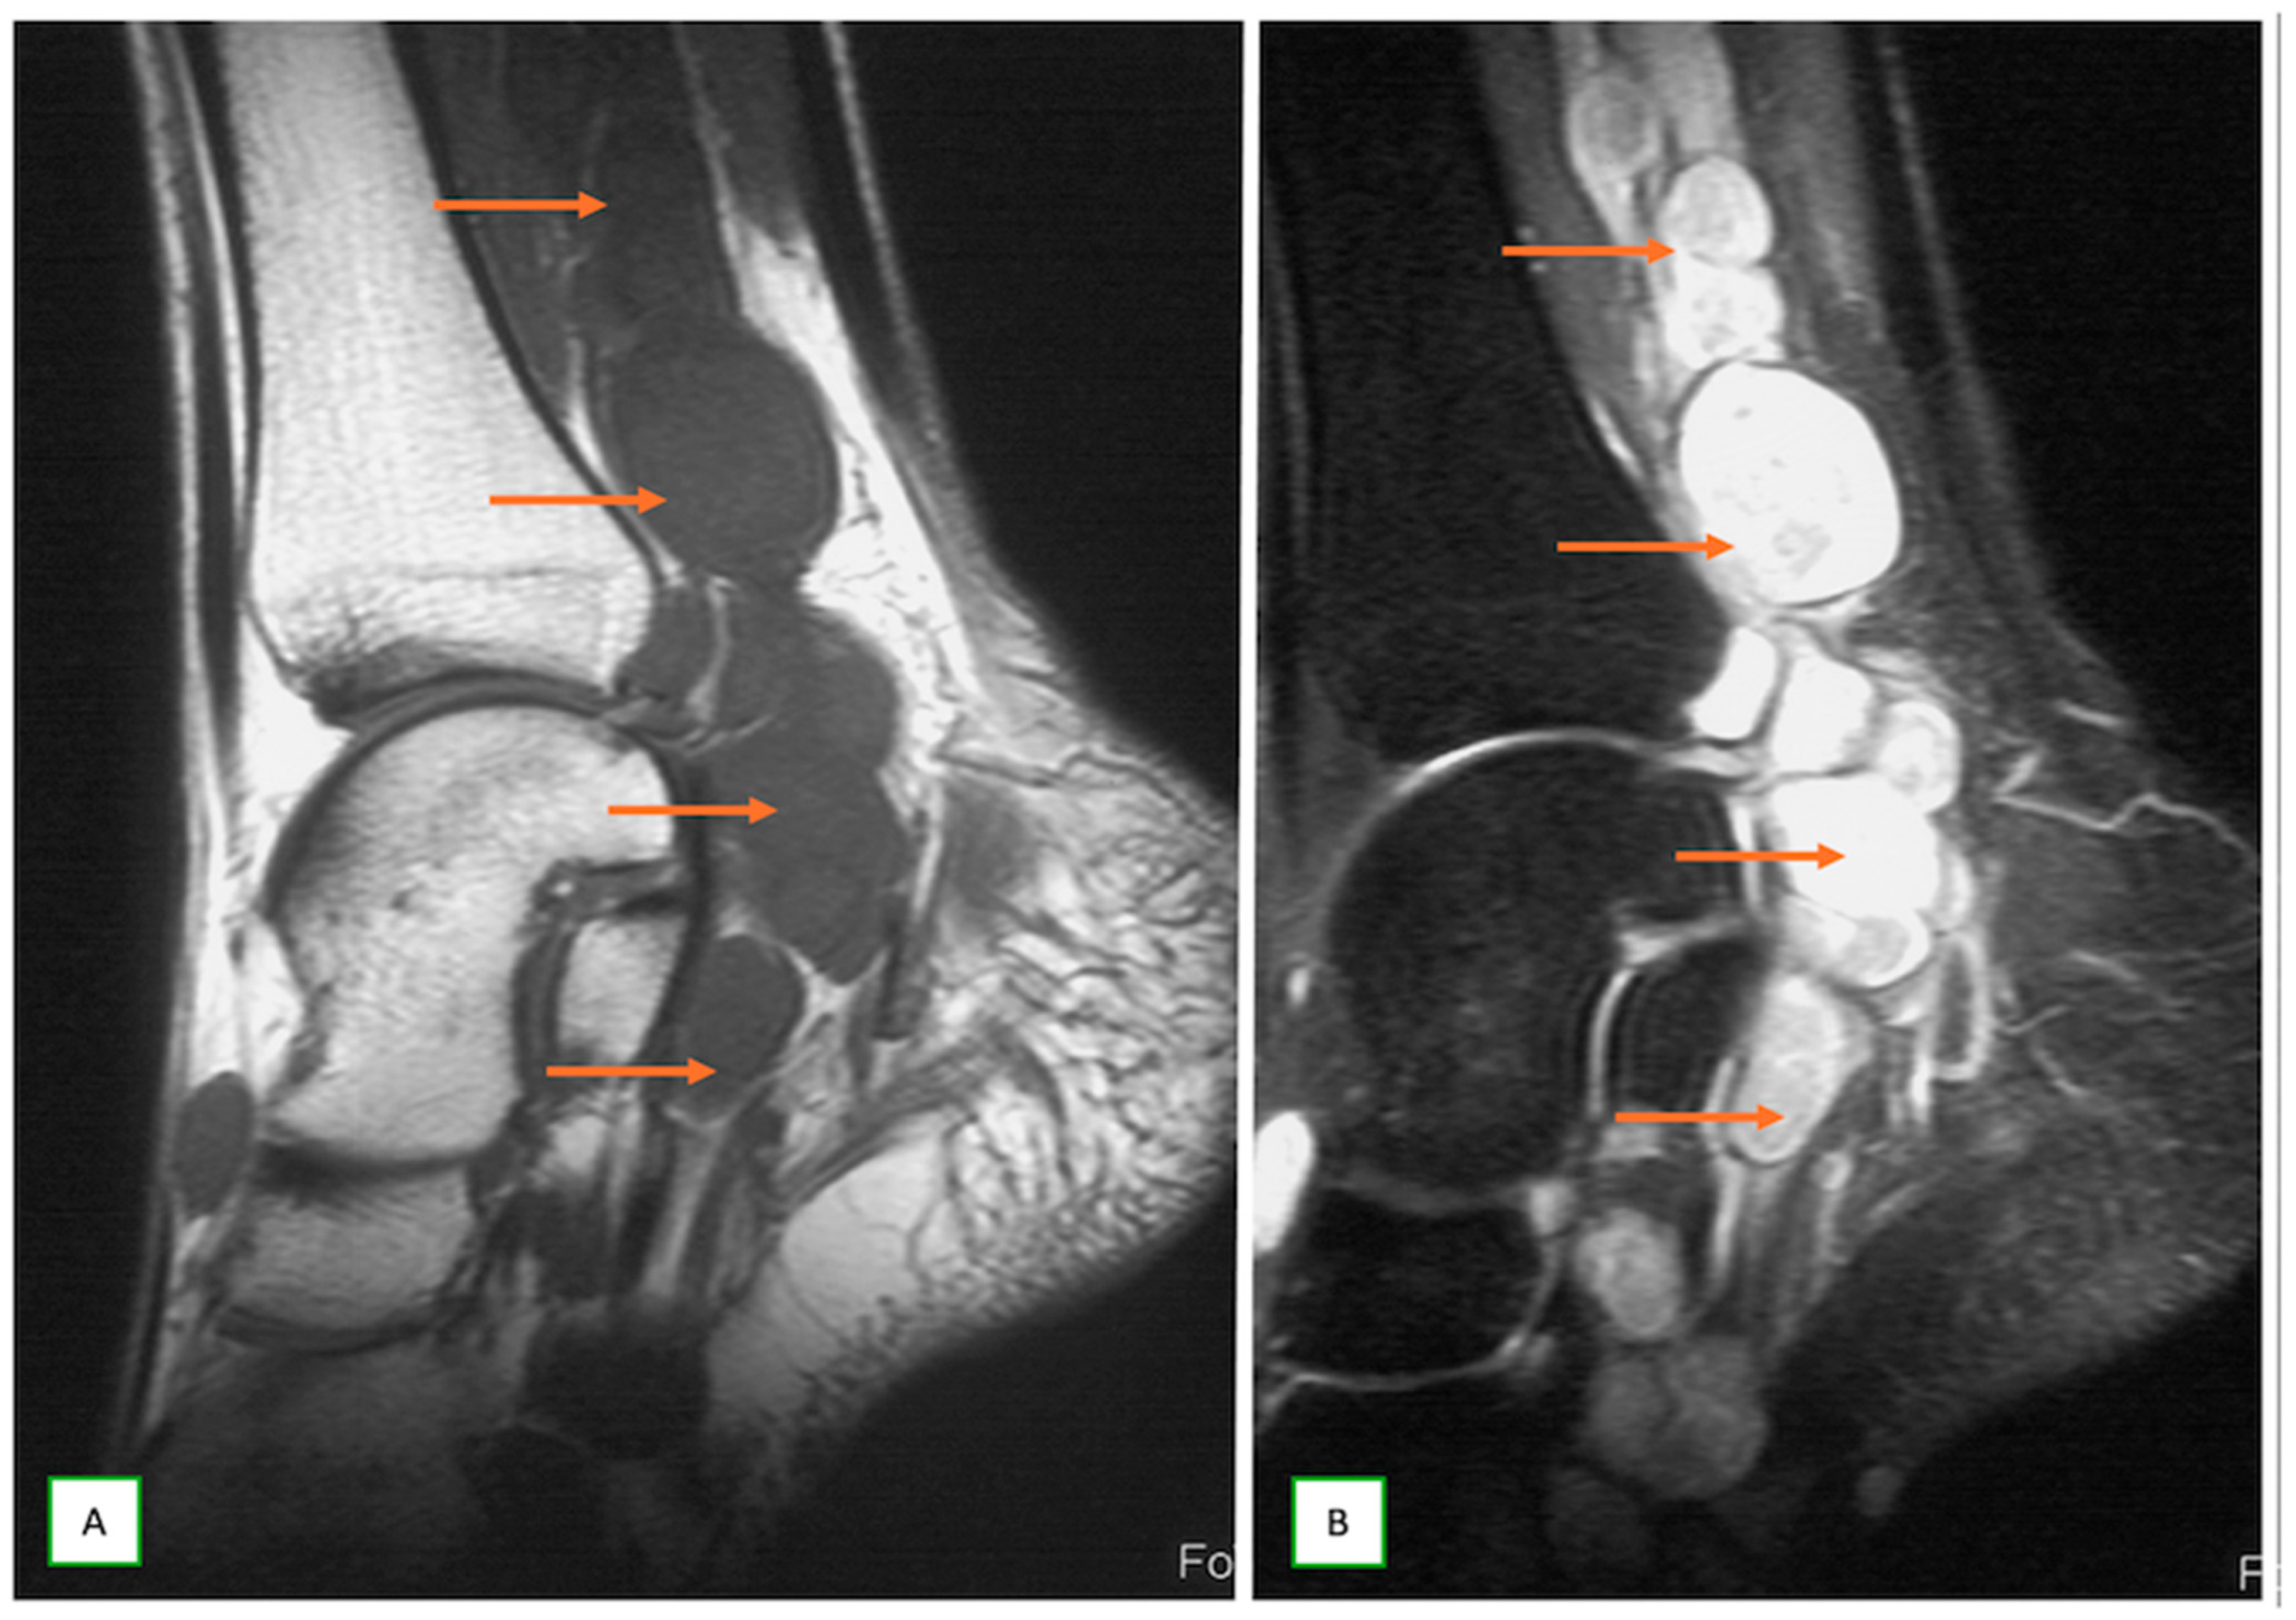

- Primary Sarcomas: Soft-tissue sarcomas are uncommon, accounting for just over 1% of adult malignancies. Synovial sarcoma, clear cell sarcoma, and epithelioid sarcomas are known to involve peripheral nerves. CT/MR reveals a large soft tissue mass with areas of necrosis or calcification and heterogeneous contrast enhancement. F-18 FDG uptake is useful for both tumor staging and treatment assessment (Figure 26, Figure 27 and Figure 28).